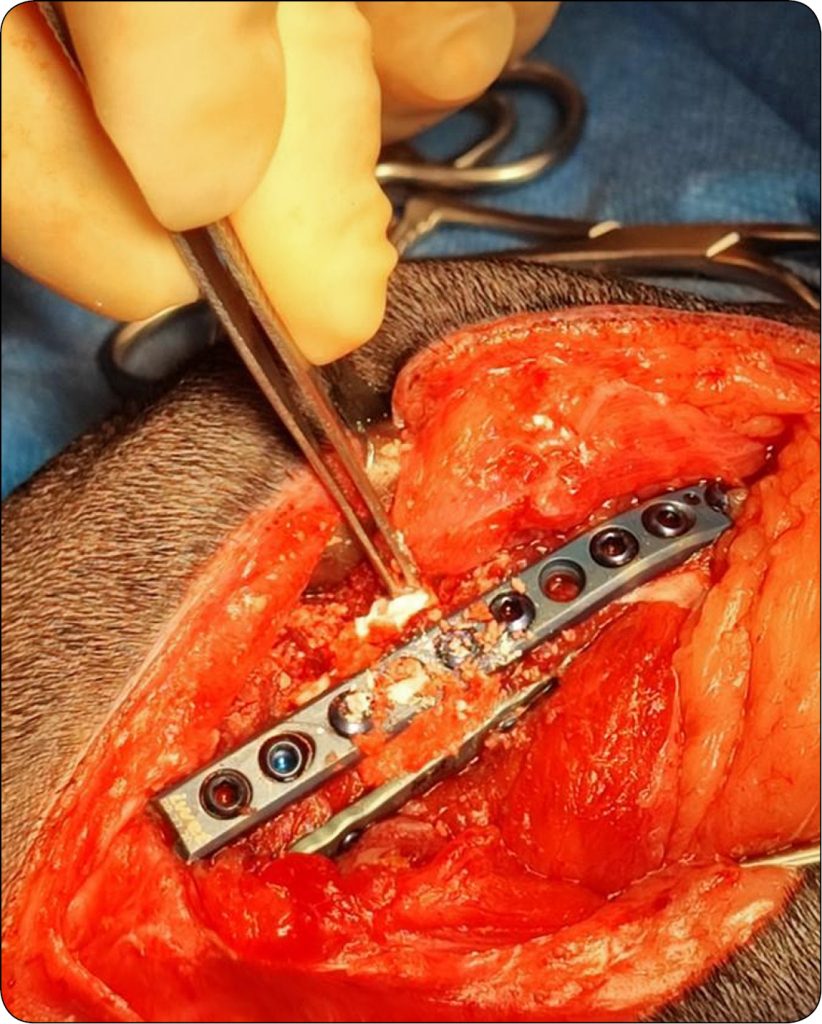

Przegląd resorbowalnych materiałów kościozastępczych dostępnych do stosowania w medycynie weterynaryjnej

Innym przykładem weterynaryjnego substytutu kości jest hydroksyapatytowo-polimerowy preparat implantacyjny (FlexiOss® VET). Materiał ten wykazuje właściwości wspomagające regenerację tkanek, jest biodegradowalny, a także może być wykorzystywany jako potencjalny nośnik leków. Jest dostępny w pięciu rozmiarach w postaci walcowatych cząstek o średnicy: 0,2 cm, 0,5 cm, 1 cm, 3 cm i 5 cm (16, 17). Analiza właściwości kompozytu nie wykazała zmian objętości, porowatości czy właściwości mechanicznych tego preparatu po inkubacji kompozytu w surowicy ludzkiej przez 5 dni, co potwierdza przydatność tego preparatu w zapobieganiu zapaleniom pooperacyjnym (18). Opisano wykorzystanie tego preparatu w leczeniu ubytków zębodołów powstałych po ekstrakcji zębów u psa. Po zastosowaniu materiału zaobserwowano gojenie się rany, bez wtórnej infekcji. Kontrola radiologiczna została przeprowadzona po wszczepieniu substytutu, a następnie po okresie 6 i 12 miesięcy. Użyty kompozyt w badaniu RTG wykonanym po 12 miesiącach nie był widoczny, a w miejscu implantacji uzyskano strukturę typowej kości (19).

Innym przykładem jest preparat w postaci hydroksyapatytu, wytwarzany z wołowej kości gąbczastej pochodzącej od bydła australijskiego (InterOss® BSE Free). Biomateriał ten jest wieloporowaty oraz hydrofilny, chemicznie i strukturalnie wykazuje podobieństwo [...]